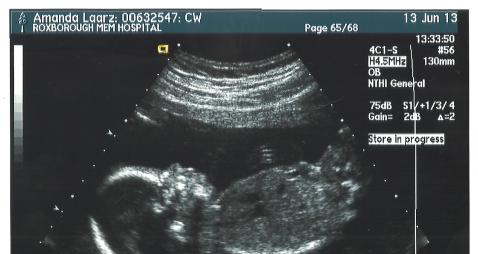

Please help, I had my 20 week ultrasound and decided with my husband that we wanted to be surprised. Now I feel like I need to know!Attachment 11992